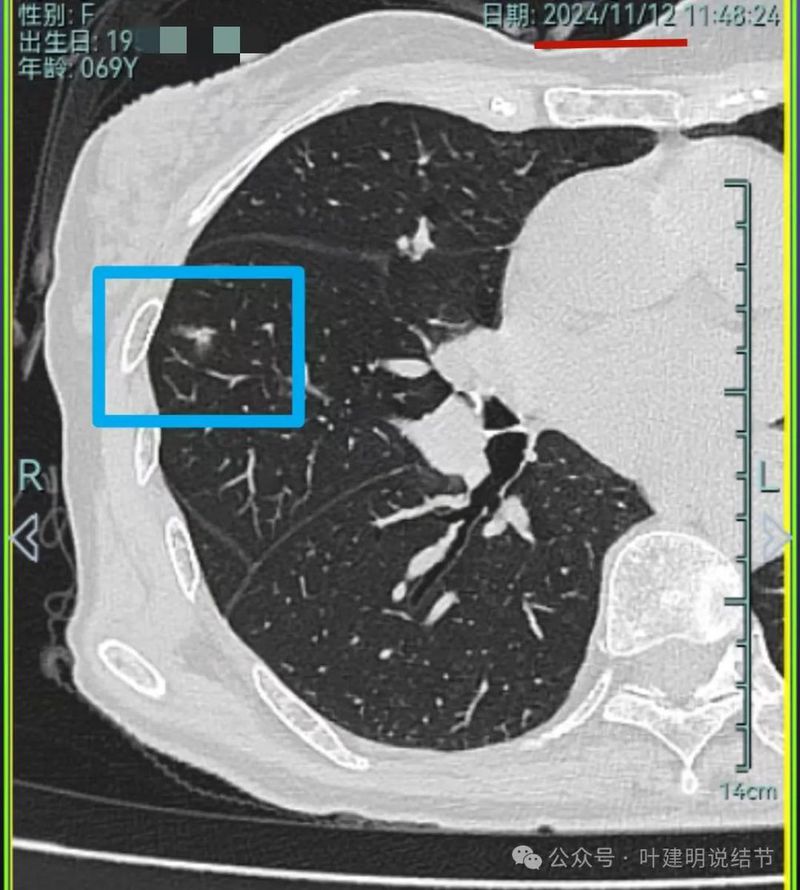

再看2024年11月复查的情况:

病灶1仍磨玻璃稍高密度,有血管进入,大小无显著进展,但密度从开始到现在是有所进展的。

病灶3仍是混合密度,伴有收缩力,但实性部分并无聚拢性,也不是密度很高的样子。

我想我们这样也来考虑问题:1、左侧已经手术的确诊是肿瘤性质,左上已经消融的也是随访持续存在的磨玻璃密度结节,虽然没有病理依据,仍然要考虑广义上来讲的肿瘤范畴,看了以前的片子,从2019年到2023年并没有显著的进展,大概是肺泡上皮不典型增生可能性大。右侧的也有磨玻璃结节与混合磨玻璃结节考虑是肿瘤范畴的。所以总体上两肺多原发早期以磨玻璃为表现的肺癌,整体风险都不大。2019年切除的左肺下叶病灶也是纯磨玻璃密度,其实如果继续随访或者只做楔形切除也并没有什么关系。这说明体质本身或者致病的因素,就是容易长磨玻璃肺癌的,即便把目前发现的都解决,后续仍可能再有新的。原因不明,致病因素仍在。2、右肺上叶红色之处从2019年开始,是逐渐进展的,当然即便是现在,也不是说危险就已经很大,考虑仍然是原位癌或者微浸润性腺癌可能性大;中叶蓝色这处乍一看像至少是微浸润,但前后对比以后发现从2019年到现在,几乎没有显著进展,这样的话慢性炎伴肺泡上皮增生或者伴纤维增生也是有可能的,至少风险并不能认为大;右肺下叶黄色这一处,使纯磨玻璃密度,整体轮廓与边界清楚,考虑是肿瘤范畴的,不典型增生可能性较大,也有可能原位癌,随访稍有进展,风险仍然不大;中叶绿色这处是慢性炎伴钙化的,靠近叶裂的地方也像慢性炎,但此处随访有所进展。不过因为有卫星灶,整体显得比较散,所以虽然恶性可能性较大,但也不能完全除外炎性的可能性。当然如果此灶确实恶性,那风险则相对较其他进展缓慢的要高一些。从目前右侧所在的这些病灶来讲,真正有一定的风险而且最为确切的是红色这处,而且应该也没有到浸润性腺癌或者说不处理会要转移很危险这种程度。3、明确了多原发早期肺癌没有办法预防与控制,也明白了目前已经存在的较明显的这些病灶总体风险的高低。我们再来考虑需不需要近期干预处理。左侧既手术过又消融过,右侧的多发病灶目前又还没有到危险很高的程度,又没有办法预防后续再有新的病灶。我个人偏保守,我觉得仍然可以半年复查随访,如果最具风险的病灶有进展并且不处理可能导致不良后果,到这样的程度再来考虑综合如何处理干预便可。4、假如右侧我们予以处理,上叶红色的以及中叶蓝色的都可以楔切,但绿色考虑良性的再进展或以后像恶性时怎么办?而若中叶切除加上叶楔切,在左侧已经手术过的情况下肺功能影响相对也不小,何况右下比较中间的位置还有桔色这处呢。当然右下这处得考虑消融。所以,我的想法还是能熬再熬下,待其他监测有变化再通盘考虑。意见供参考!